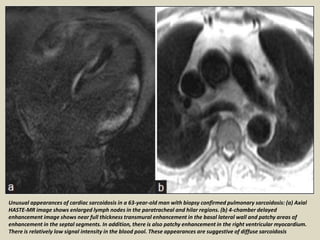

Unusual appearances of cardiac sarcoidosis in a 63-year-old man with biopsy confirmed pulmonary sarcoidosis: (a) Axial

HASTE-MR image shows enlarged lymph nodes in the paratracheal and hilar regions. (b) 4-chamber delayed

enhancement image shows near full thickness transmural enhancement in the basal lateral wall and patchy areas of

enhancement in the septal segments. In addition, there is also patchy enhancement in the right ventricular myocardium.

There is relatively low signal intensity in the blood pool. These appearances are suggestive of diffuse sarcoidosis